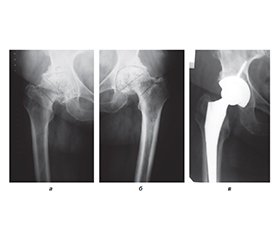

Актуальність. Проблема діагностики та профілактики післяопераційних коагулопатій доволі актуальна у сучасній ортопедії, оскільки в Україні й за кордоном зростає кількість операцій ендопротезування пацієнтам з різною патологією кульшових суглобів. Мета: на основі аналізу факторів ризику розвитку венозних тромбоемболічних ускладнень (ВТЕУ) у хворих із патологією кульшового суглоба до та після операції ендопротезування обґрунтувати комплекс заходів їх профілактики. Матеріали та методи. Пацієнтів, яким проводилось ендопротезування кульшового суглоба, було розділено на групи: І група — низького ступеня ризику віком 20–40 років (n = 13); ІІ група — помірного ступеня ризику віком 41–60 років (n = 45); ІІІ група — високого ступеня ризику віком 61–80 років (n = 42). Для оцінки ступеня ризику тромботичних ускладнень використовували методику, аналогічну шкалі J.F. Caprini. Результати. Аналіз тромботичних ускладнень у досліджуваних групах хворих після операції тотального ендопротезування кульшового суглоба у порівнянні з даними наукової літератури показав, що ускладнення у вигляді тромбоемболії легеневої артерії у наших пацієнтів не спостерігалося, а за даними літератури — від 1,08 до 30 %, тромбози глибоких вен нижніх кінцівок у нашому дослідженні — 4,65 %, а за даними літератури — 10–20 % (зменшення в середньому на 5,35 %). Набряк нижніх кінцівок (хронічна венозна недостатність) у наших пацієнтів — 15,5–20,9 %, за даними літератури — 17–25 % (зменшення в середньому на 3 %). Висновки. Тромбопрофілактика венозних тромбоемболічних ускладнень при операції тотального ендопротезування кульшового суглоба потребує індивідуального підходу до пацієнтів з огляду на фактори ризику як у доопераційному, так і у післяопераційному періодах. Запропонована нами програма профілактики в досліджуваних пацієнтів, якщо порівнювати з даними літератури, дозволила зменшити кількість тромботичних ускладнень: у І групі хворих з низьким ступенем ризику ці ускладнення не відмічалися, у ІІ і ІІІ групах тромбози глибоких вен нижніх кінцівок зменшилися на 5,35 %, набряки нижніх кінцівок — на 3 %, гематоми у ділянці операції — на 1,5 %. Отримані дані свідчать про ефективність і доцільність застосування запропонованого нами комплексу заходів тромбопрофілактики у хворих після ендопротезування кульшового суглоба.

Background. The problem of diagnosis and prevention of postoperative coagulopathies is quite relevant in modern orthopaedics, since an increasing number of patients with various pathologies of the hip joints undergo arthroplasty both in Ukraine and abroad. The purpose: based on the analysis of risk factors for the development of venous thromboembolic complications in patients with hip joint pathology after arthroplasty, to substantiate a set of measures for their prevention. Materials and methods. Patients who underwent hip arthroplasty were divided into the following groups: group I — low risk, 20–40 years old (n = 13); group II — moderate risk, 41–60 years old (n = 45); group III — high risk, 61–80 years old (n = 42). To assess the risk of thrombotic complications, a method similar to the J.A. Caprini score was used. Results. Analysis of thrombotic complications in the studied groups of patients after total hip replacement compared to the data of the scientific literature showed that complications in the form of pulmonary embolism were not observed in our patients. According to the literature, they are found in 1.08–30 % of cases. Deep vein thrombosis of the lower extremities was detected in 4.65 and 10–20 % of patients, respectively (an average decrease of 5.35 %), oedema of the lower extremities (chronic venous insufficiency) — in 15.5–20.9 and 17–25 % of cases (an average decrease of 3 %). Conclusions. Thromboprophylaxis of venous thromboembolic complications during total hip arthroplasty requires an individual approach to patients, taking into account risk factors both in the pre-operative and postoperative periods. The prevention program we proposed in the studied patients, compared to the literature data, allowed us to reduce the number of thrombotic complications: in group I of patients with a low risk, these complications were not observed, in groups II and III, deep vein thrombosis of the lower extremities decreased by 5.35 %, oedema of the lower extremities by 3 %, hematomas in the surgical area by 1.5 %. The data obtained indicate the effectiveness and feasibility of using a set of thromboprophylaxis measures proposed by us in patients after hip arthroplasty.